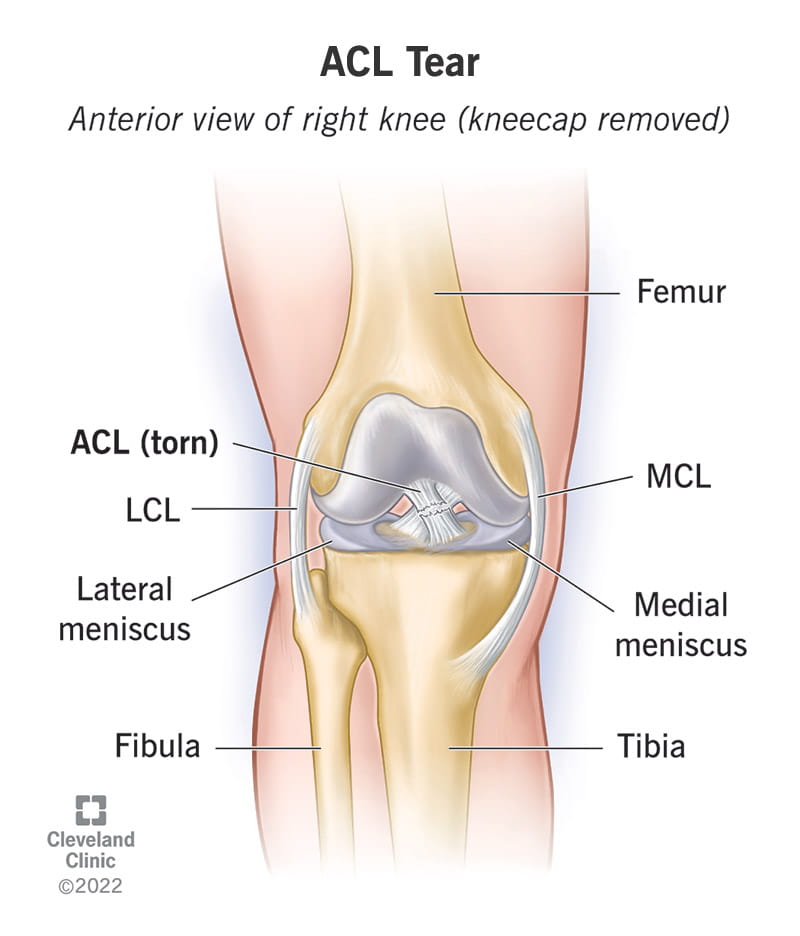

Pengenalan kepada ACL Injury

ACL ialah ligamen penting di dalam lutut yang menyambungkan tulang paha (femur) ke tulang betis (tibia). Ia berfungsi untuk mengawal pergerakan hadapan tibia dan memberikan kestabilan pada sendi lutut.

Apabila ligamen ini diregang atau terkoyak, ia dikenali sebagai Acl Injury. Punca utama kecederaan ini termasuk: